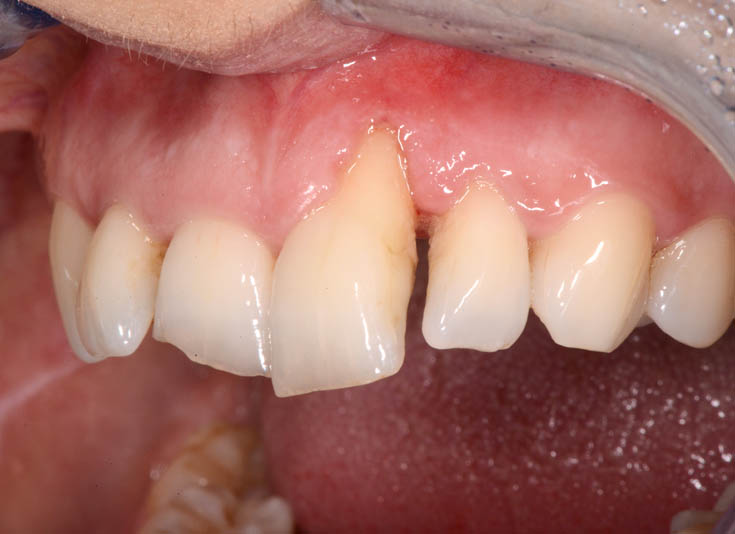

The healing has now reached a 5-year follow-up.

The patient is absolutely delighted with the outcome, but I have repeatedly (and unsuccessfully) encouraged her to undergo a small additional graft to address the minor residual recession on tooth 21.